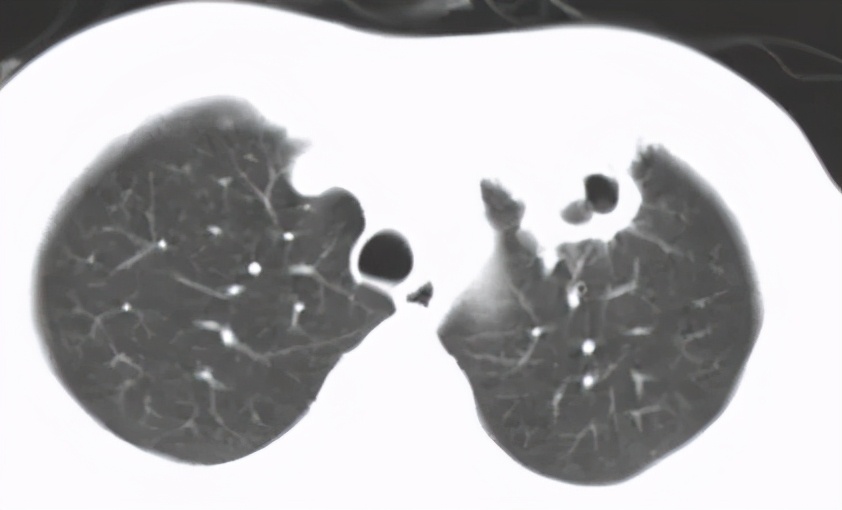

病例3 :

男,50岁,发热1月;骨穿:感染象;胸部CT:右肺阴影,纵膈淋巴结肿大。

这位患者入院时,完全像是白血病化疗过程中出现的改变,那么,会不会是白血病的肺部浸润呢?但是白血病肺部浸润较多见间质的浸润,而这位患者病变呈片状,是实质性的浸润……我们给患者做了骨穿,证实是感染象。

最终痰抗酸染色阳性、血HIV阳性;患者为同性恋。